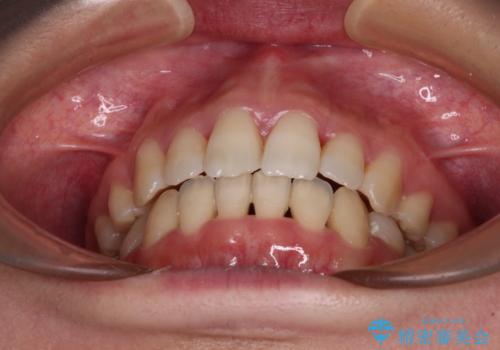

Eラインを改善したい ハーフリンガルによる抜歯矯正

- 口元の突出感を気にして来院された患者様です。

上下左右の第一小臼歯4本を抜歯して口元を下げる治療計画としました。

舌の突出癖が強く、口元を引っ込める力に拮抗してしまい、抜歯スペースを閉じるまでに時間がかかりました。

また途中出産もありましたが、無事に治療を終えることができました。